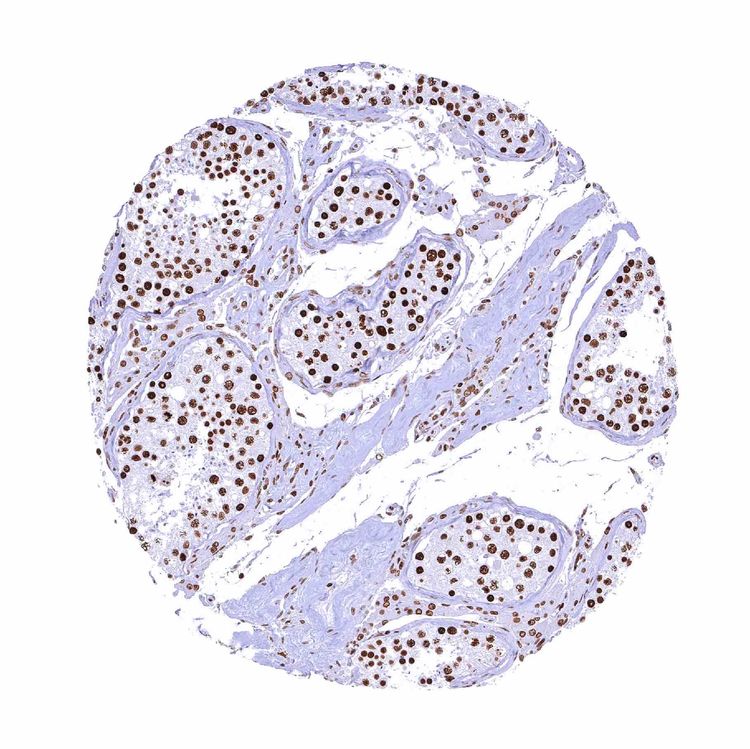

Testis